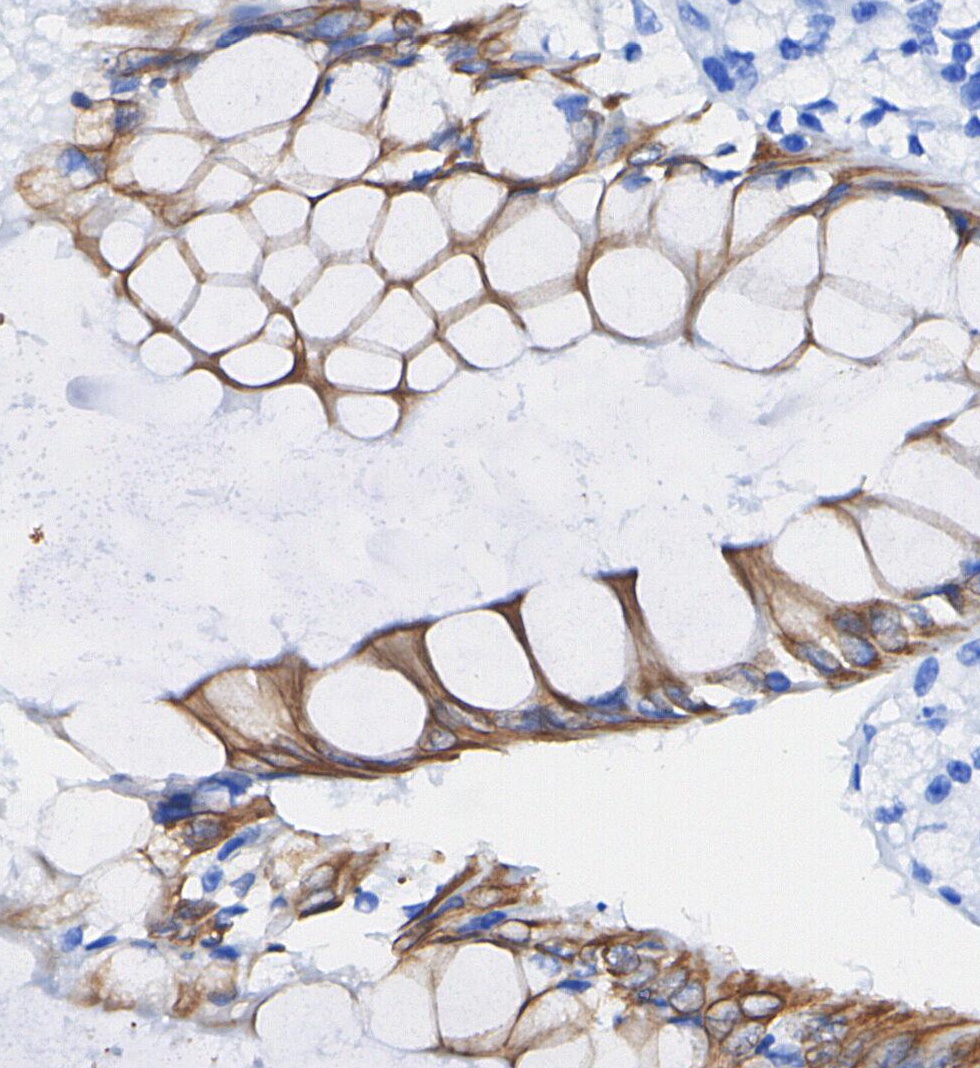

• Immunohistochemical analysis of formalin fixed paraffin embedded human Colorectal cancer tissue with F1153 at 1/100 dilution.